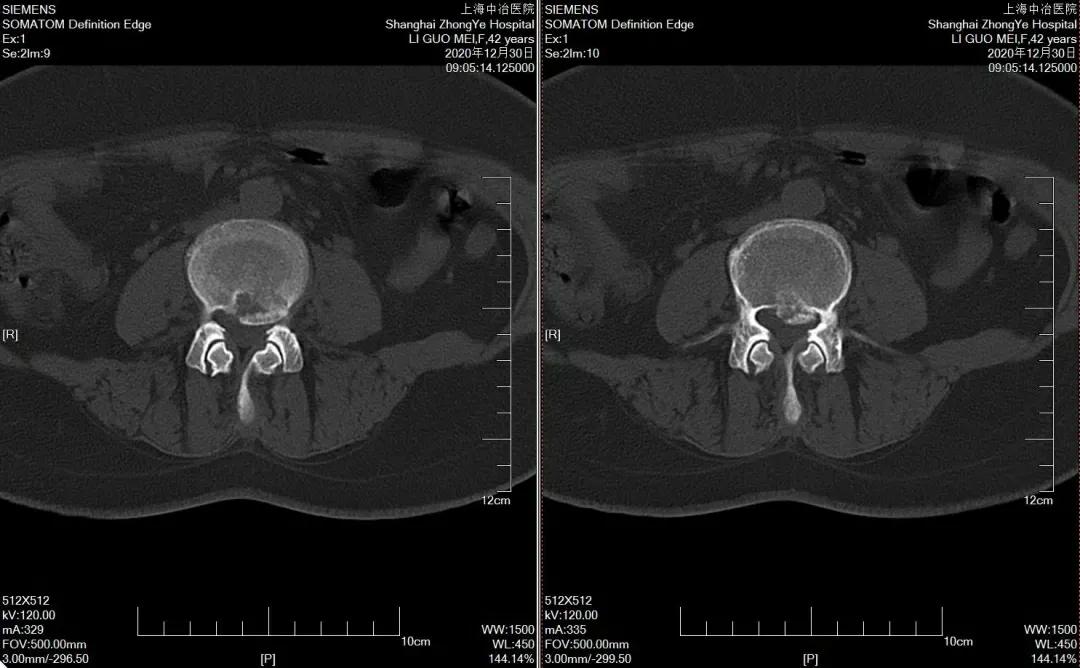

CT

可显示骨性椎管形态,黄韧带是否增厚,椎间盘突出的大小及方向,是否伴有钙化等。